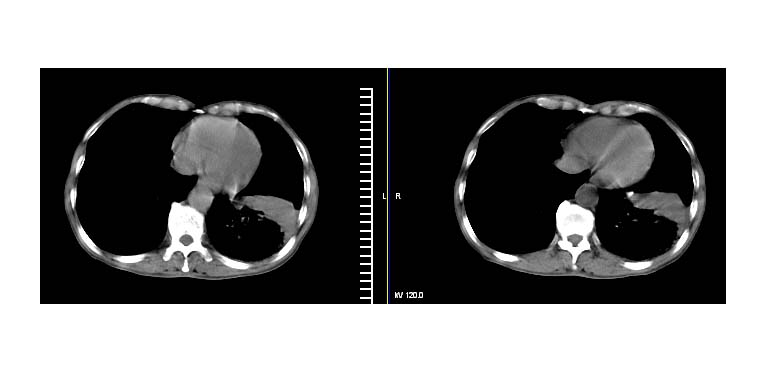

标题: CT11019:男性,66岁。发烧5-6天。治疗后无明显好转。 [打印本页]

标题: CT11019:男性,66岁。发烧5-6天。治疗后无明显好转。

阻塞性肺炎并不张,建议抗炎治疗后复查或增强

左下肺中心性肺癌伴下肺不张及周围阻塞性炎症

考虑左肺下叶炎症合并叶间裂积液,建议抗炎治疗后复查

左下肺实变,考虑炎症